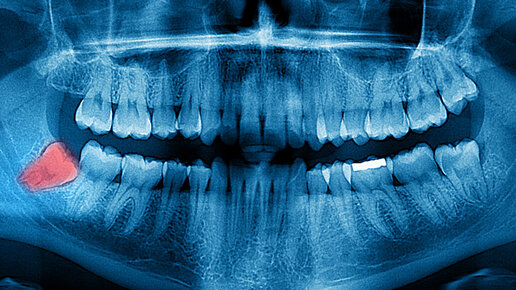

Когда человек появляется на свет, у него нет ни одного зуба. На первом году жизни постепенно прорезаются маленькие молочные зубы. При достижении возраста 5–7 лет молочный прикус постепенно меняется: временные зубы начинают выпадать, освобождая место для постоянных зубов. У взрослого человека максимальное количество зубов - 32 (в отдельных случаях их бывает и больше, это так называемые сверхкомплектные зубы - явление редкое). Четыре из них, самые крайние в верхнем и нижнем зубном ряду – это зубы мудрости...

Наши далекие предки добыли огонь примерно 1,6 миллионов лет назад, что сильно изменило их привычный рацион. До этого знаменательного события зубы были единственным инструментом, позволяющим справляться с самой жесткой и сырой пищей, а челюсть первобытных людей была более широкой и насчитывала дополнительные коренные зубы. Но так как огонь делал пищу мягче, размер челюсти древних людей начал меняться – она становилась все меньше и некоторым зубам стало не хватать места. В конечном итоге миллионы лет эволюции превратили зубы мудрости в рудимент – орган, утративший свою ценность...